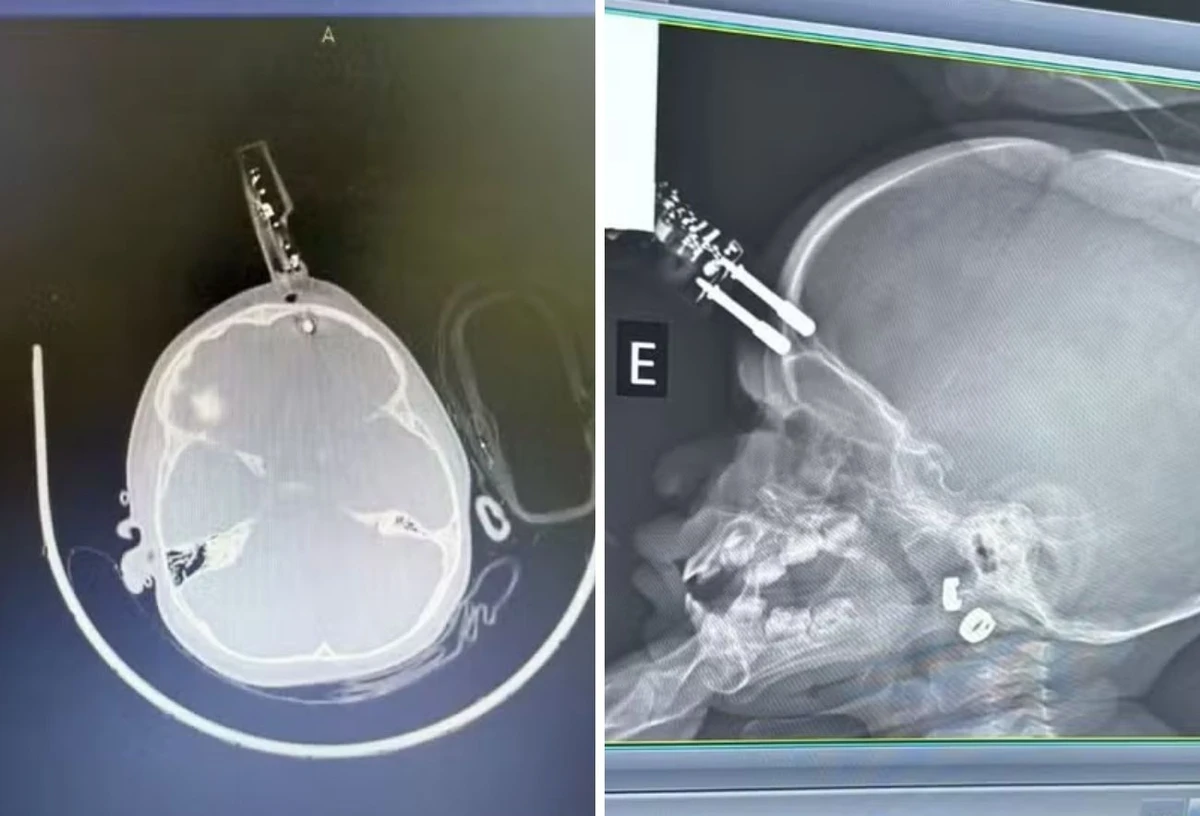

Exames mostram o aparelho que perfurou a a região frontal do crânio

Exames mostram o aparelho que perfurou a a região frontal do crânio Crédito: Arquivo pessoal

Uma bebê de um ano ficou com um carregador cravado na testa após cair da cama, na última terça-feira (13). A mãe da criança foi ao banheiro no momento do acidente, informou o médico que atendeu a menina, Bruno Castro, em entrevista ao G1. O caso aconteceu na cidade de Divinópolis, interior de Minas Gerais.

Ainda segundo ele, a bebê estava com o carregador na mão no momento da queda, o que fez com que o aparelho atingisse a cabeça e perfurasse a região frontal do crânio.

A criança passou por uma cirurgia de urgência para retirada do objeto e reconstrução da área atingida. O médico acrescentou que ela segue internada e recebe antibiótico profilático. Ele também revelou que a paciente não apresenta sinais de sequelas.

“Crianças têm uma plasticidade neuronal muito boa, o que aumenta as chances de recuperação sem sequelas”, acrescentou em entrevista ao G1. Ainda assim, a menina vai passar por acompanhamento neurológico contínuo em caso de problemas futuros.